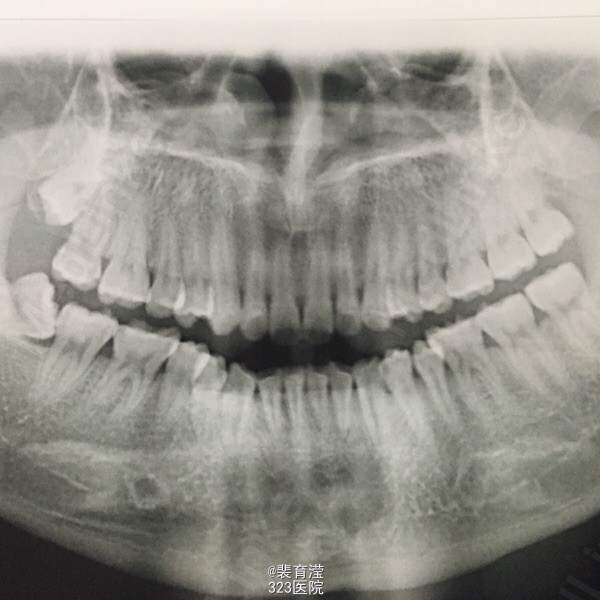

检查:右侧上颌第一磨牙,颊部前庭沟底,直径1.5mm 囊肿,探不适,波动感。 右下第三磨牙 近中阻生

诊断:异物囊肿 右下第三磨牙阻生 处理:1.局麻下切除异物囊肿,缝合,止血。 2.右下第三磨牙局麻下 拔除 搔刮牙槽窝 止血。